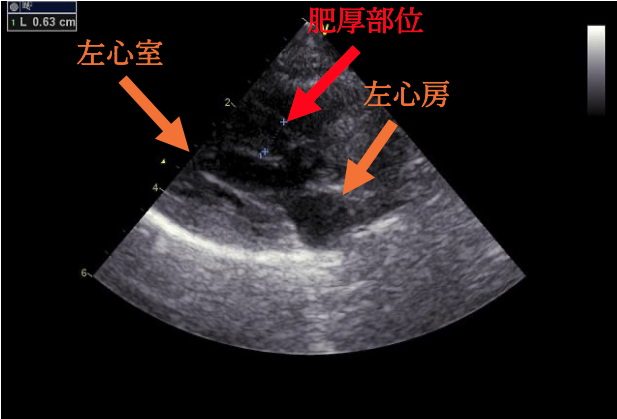

今回の心臓超音波検査では、左心室の壁が厚くなり、大動脈に血液を送り出す出口が少し狭くなっていることが確認されました。ただし、ねこちゃんには症状がなく、検査上でも重度ではなかったため、今回はお薬を使わずに経過観察となりました。

肥大型心筋症とは、左心室の壁が厚くなってしまい、血液をうまく送り出せなくなる病気です。